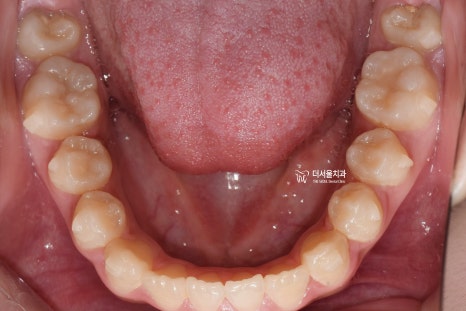

『구강 내 사진』

성장교정 이 필요한 이유는,

구강 내 사진에서도 뚜렷히 찾아볼 수 있습니다.

유치가 빠지면서 영구치아가 올라오고 있는

혼합치열기에서, 영구치가 올라올 수 있는

충분한 공간을 확보하면서

턱의 위치를 바로 잡는것이 핵심포인트입니다.

우선 여기서 봐야 될 큰 문제는

1) 절단교합(Edge to edge bite) 입니다.

윗니가 아랫니를 물고 있어야 되는데,

서로 절단연끼리 맞닿고 있죠.

그러면서, 성장교정 을 통해서

위턱의 크기를 발달시키며

아래턱은 억제시켜야 되는 상황입니다.